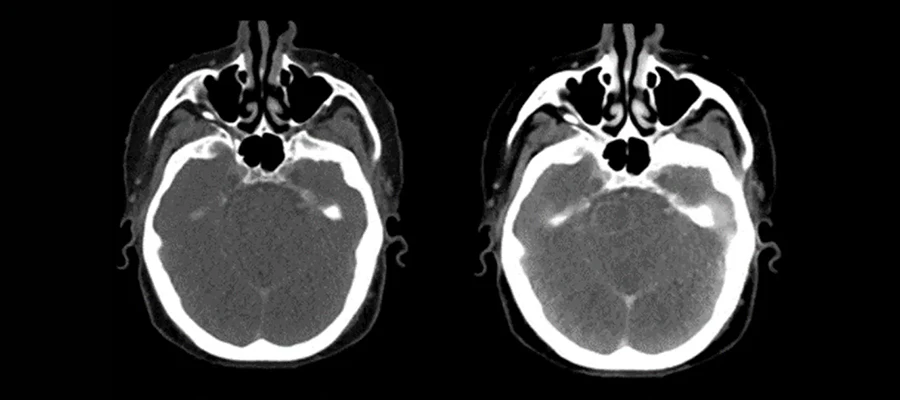

Gelişmiş görüntüleme yöntemleri arasında yer alan bu teknik, farklı enerji seviyeleri kullanılarak detaylı analiz yapılmasını sağlar. Dual enerji BT, iki farklı X-ışını enerjisi ile çekim yaparak dokuların yapısal ve kimyasal özelliklerini ayırt edebilen bir bilgisayarlı tomografi yöntemidir. Bu sayede aynı dokunun farklı bileşenleri daha net şekilde görüntülenebilir. Kontrastlı dual enerji BT, damar ve yumuşak doku detaylarını daha belirgin hale getirirken, kontrastsız dual enerji BT bazı durumlarda yeterli olabilir. İşlem sırasında hasta kısa süre hareketsiz kalmalıdır. Dual enerji BT, özellikle taş analizi, tümör değerlendirmesi ve damar hastalıklarının incelenmesinde kullanılır. Görüntüler bilgisayar ortamında işlenir ve uzman tarafından analiz edilir. Çekim süresi genellikle birkaç dakika sürer ve hızlı sonuç elde edilir. Modern tıpta dual enerji BT, daha detaylı teşhis için önemli bir yöntem olarak kabul edilir.

Farklı dokuların daha ayrıntılı şekilde incelenmesini sağlayan yöntemler, teşhis sürecinde önemli avantajlar sunar. Dual enerji BT, farklı enerji seviyeleri sayesinde dokuların kimyasal yapısını ayırt ederek daha doğru analiz yapılmasına imkân tanır. Özellikle böbrek taşlarının türünü belirlemek, tümörleri değerlendirmek ve damar hastalıklarını incelemek için kullanılır. Kontrastlı dual enerji BT, damar ve yumuşak doku detaylarını netleştirirken, kontrastsız dual enerji BT bazı durumlarda yeterli olabilir. İşlem sırasında hasta kısa süre hareketsiz kalmalıdır. Görüntüler bilgisayar ortamında işlenir ve uzman tarafından değerlendirilir. Dual enerji BT, modern tıpta doğru teşhis ve tedavi planlamasında önemli bir rol oynar.

Görüntüleme teknolojilerindeki yenilikler sayesinde dokuların daha detaylı analizi mümkün hale gelmiştir. Dual enerji BT, iki farklı X-ışını enerjisi kullanarak dokuların yoğunluk ve kimyasal özelliklerini karşılaştırır. Bu sayede aynı bölgede bulunan farklı dokular ayrıştırılabilir. Kontrastlı dual enerji BT, damar ve yumuşak doku detaylarını belirgin hale getirirken, kontrastsız dual enerji BT bazı durumlarda yeterli olabilir. İşlem sırasında hasta kısa süre hareketsiz kalmalıdır. Görüntüler bilgisayar ortamında işlenir ve analiz edilir. Dual enerji BT, özellikle karmaşık vakaların değerlendirilmesinde önemli avantaj sağlar. Modern tıpta bu teknoloji, detaylı ve güvenilir görüntüleme sunar.

Farklı dokuların ayırt edilmesi, gelişmiş görüntüleme teknikleri sayesinde mümkün hale gelmiştir. Dual enerji BT, iki farklı enerji seviyesi kullanarak dokuların yoğunluk farklarını analiz eder. Bu sayede kemik, yumuşak doku ve sıvılar net şekilde ayrıştırılabilir. Kontrastlı dual enerji BT, damar ve lezyon detaylarını belirgin hale getirirken, kontrastsız dual enerji BT bazı durumlarda yeterli olabilir. İşlem sırasında hasta kısa süre hareketsiz kalmalıdır. Görüntüler bilgisayar ortamında işlenir ve analiz edilir. Dual enerji BT, modern tıpta detaylı doku analizi için önemli bir yöntemdir.

Farklı doku türlerinin ayrıntılı şekilde incelenmesini sağlayan bu yöntem, geniş kapsamlı bilgi sunar. Dual enerji BT, dokuların yoğunluk ve kimyasal yapısını analiz ederek taş, tümör ve damar hastalıklarını net şekilde gösterir. Bu sayede hastalıkların yapısı ve yayılımı hakkında detaylı bilgi elde edilir. Kontrastlı dual enerji BT, damar ve lezyon detaylarını daha belirgin hale getirir. Kontrastsız dual enerji BT bazı durumlarda yeterli olabilir. Görüntüler bilgisayar ortamında işlenir ve uzman tarafından analiz edilir. Dual enerji BT, modern tıpta detaylı inceleme için önemli bir yöntemdir ve doğru teşhis sürecine katkı sağlar.